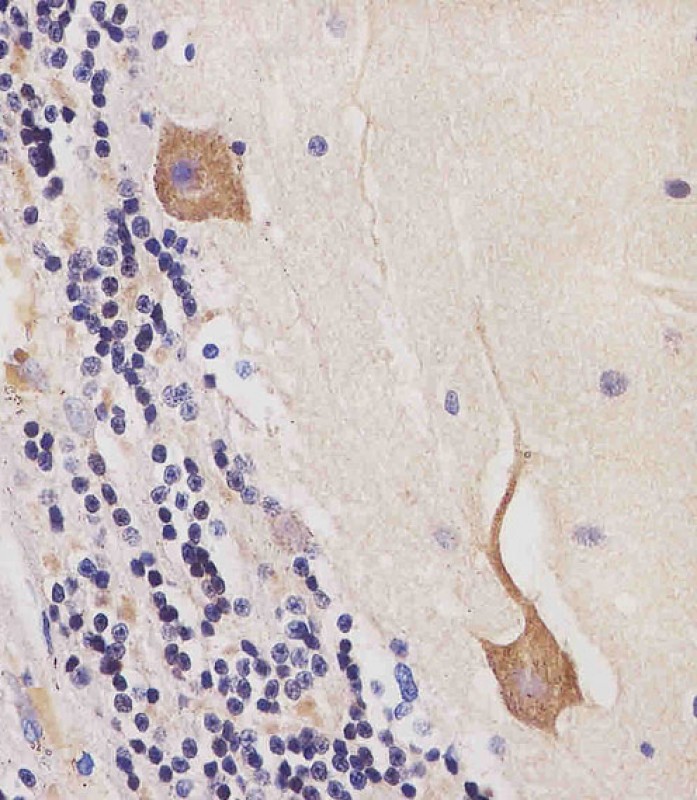

| IHC | 1/100-1/500 | Human,Mouse,Rat |

The CAMK2β (Calcium/Calmodulin-Dependent Protein Kinase II Beta) antibody is a crucial tool for studying the function and expression of the CAMK2β protein, a member of the Ca²⁺/calmodulin-dependent kinase family. CAMK2β plays a pivotal role in calcium-mediated signaling pathways, particularly in the brain, where it regulates synaptic plasticity, neuronal development, and memory formation. It exists as part of a multimeric holoenzyme, often forming heteromeric complexes with other isoforms (e.g., CAMK2α). Unlike CAMK2α, which is predominantly expressed in excitatory neurons, CAMK2β is more widely distributed across tissues, including the heart and immune cells, and is implicated in diverse cellular processes such as cytoskeletal reorganization and gene transcription.

Antibodies targeting CAMK2β enable researchers to detect and quantify the protein in various experimental settings, including Western blotting, immunohistochemistry, and immunofluorescence. These antibodies are essential for investigating CAMK2β's post-translational modifications (e.g., autophosphorylation at Thr287) and its dynamic activation in response to calcium signaling. Dysregulation of CAMK2β has been linked to neurological disorders (e.g., Alzheimer’s disease, autism spectrum disorders) and cardiac arrhythmias, making its study clinically relevant. Validation of CAMK2β antibodies typically involves knockout controls or isoform-specificity tests to ensure minimal cross-reactivity with other CAMK2 family members. Ongoing research continues to explore its dual roles as a kinase and a structural scaffold in cellular signaling networks.